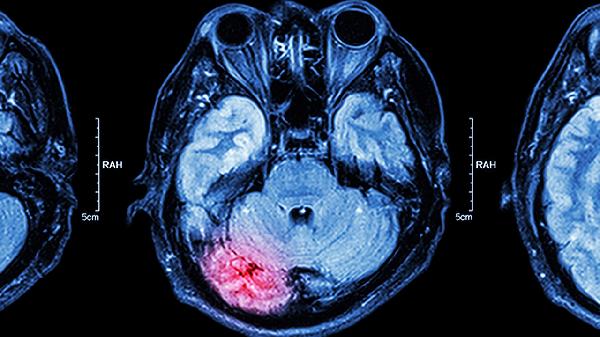

4、前庭性眩晕

脑立清丸对前庭功能障碍引发的旋转性眩晕有一定改善作用,尤其适合伴随恶心呕吐的肝阳上亢患者。用药期间应避免突然起身或头部剧烈转动。同类治疗药物包括眩晕宁片、养血清脑颗粒等。